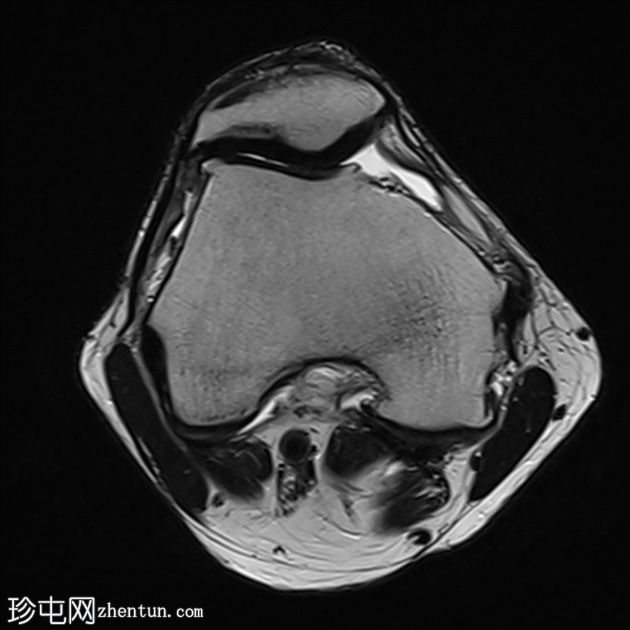

轴向PD脂肪饱和度

T2和PD脂肪饱和序列上可见多处轻微高信号区,位于股四头肌腱远端、前交叉韧带、内侧副韧带近端1/3内表面深层、腘肌腱附着处。

少量膝关节积液。

其他发现包括:前交叉韧带腱鞘囊肿、膝关节后外侧轻度肌间液信号和轻度软骨软化。

印象:这些发现提示痛风性关节炎伴单钠尿酸盐晶体沉积。